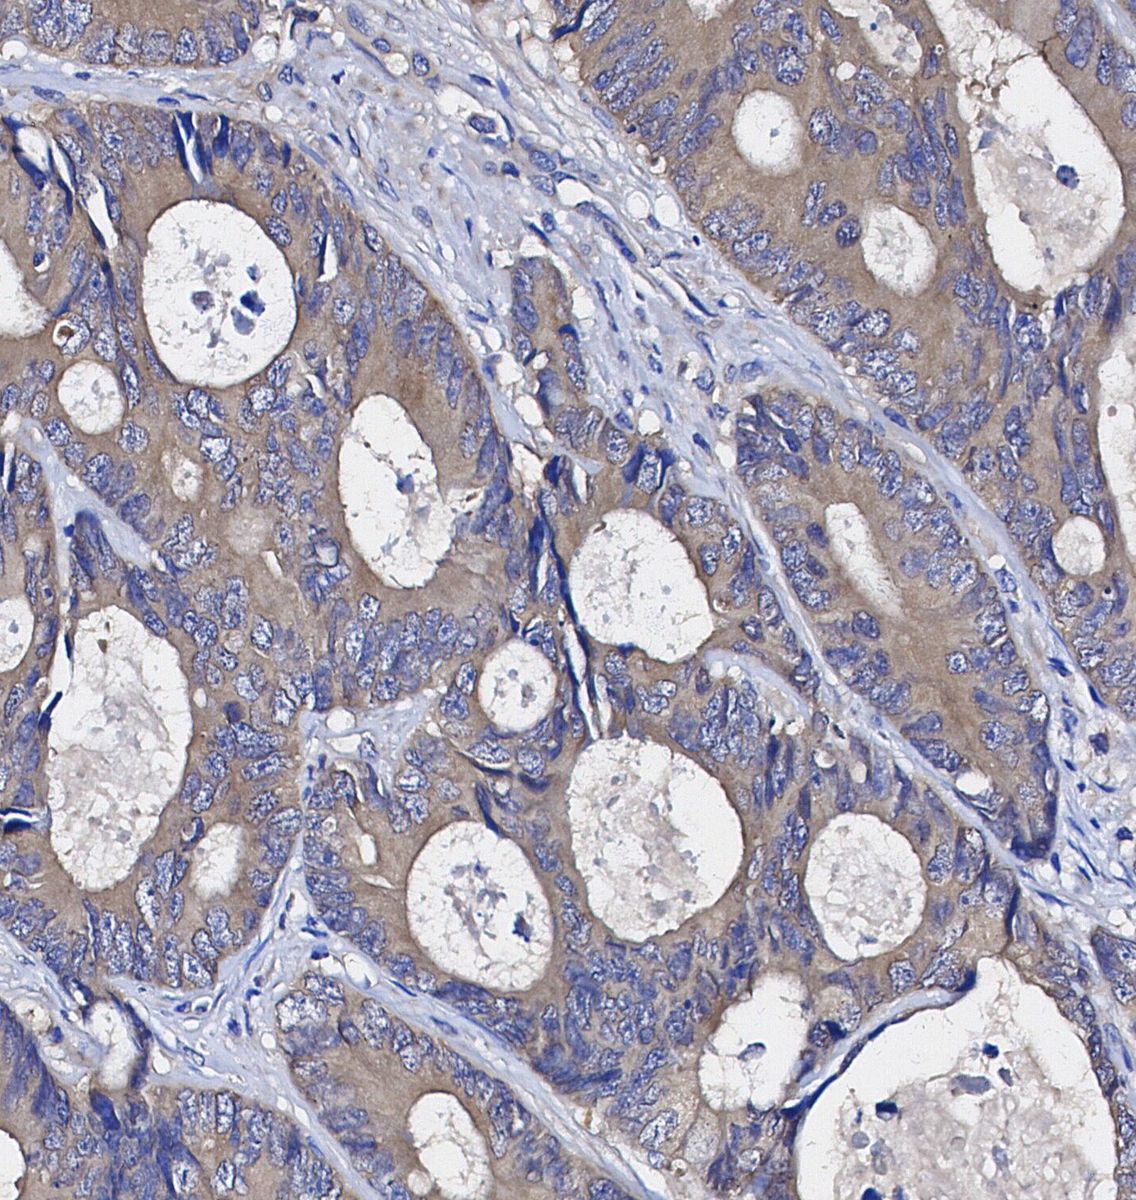

• Immunohistochemical analysis of formalin fixed paraffin embedded human Colorectal cancer tissue with F1179 at 1/100 dilution.